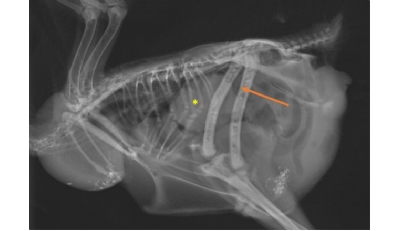

Infections à Macrorhabdus ornithogaster chez les Psittacidés - P 17